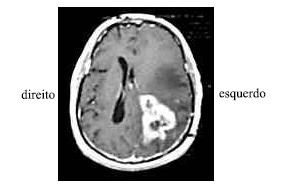

Uma senhora de 55 anos de idade, viúva, diabética e hipertensa, deu entrada no pronto-socorro após ter desmaiado em sua casa. O seu neto de 9 anos de idade informou que viu a avó cair da própria altura enquanto ela ia se contorcendo, tendo, depois, se debatido no chão e não acordado mais. Ao exame inicial, a paciente apresentava-se não-responsiva aos comandos verbais, movimentava os membros esquerdos, mas só retirava os membros direitos aos estímulos dolorosos (sem postura patológica). Foi verificada anisocoria sutil, com a pupila esquerda maior que a direita. A família referiu ao clínico geral que a paciente estava cada vez mais confusa nas últimas semanas, e atribuiu tal fato aos descuidos da paciente com o diabetes.

Considere que a paciente referida no texto, ao se encontrar estável, tenha sido submetida a uma ressonância nuclear magnética com contraste, cujo resultado é mostrado na figura acima. Diante do quadro clínico em tela, assinale a opção acerca da conduta mais adequada em relação a essa paciente.

Considerando as informações acima e a conduta a ser tomada em relação à paciente em apreço, assinale a opção incorreta.